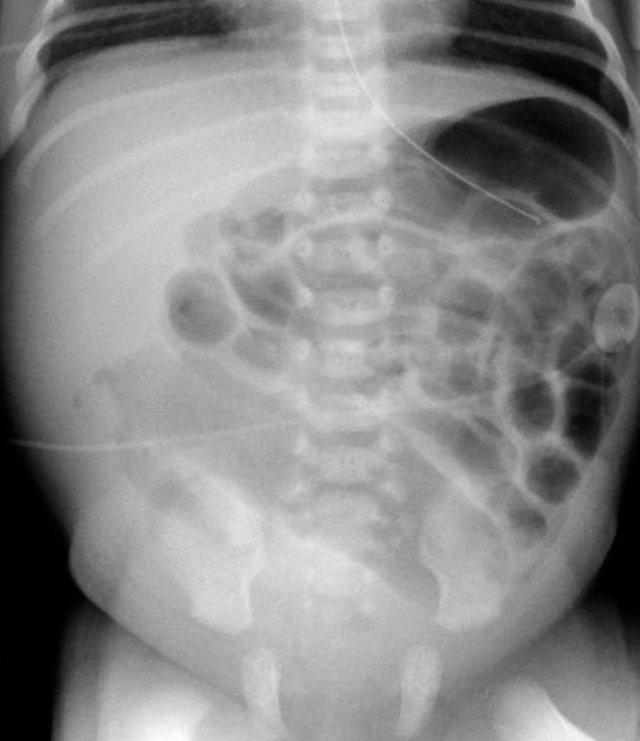

Hình ảnh cho thấy một trẻ sơ sinh với các quai ruột giãn.

Không có khí trong trực tràng.

Bệnh nhân này bị tắc ruột phân su.